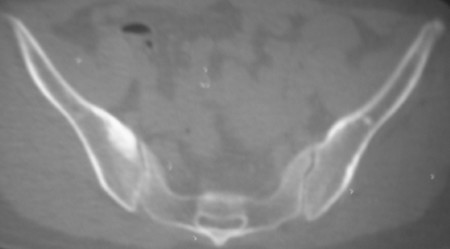

标题: CT7246: F,30岁,下腰痛,同事的片子,请老师们看看,初 [打印本页]

标题: CT7246: F,30岁,下腰痛,同事的片子,请老师们看看,初

典型的致密性髂骨炎

典型的双侧骶髂关节致密性骨炎.

何谓髂骨致密性骨炎?髂骨致密性骨炎是发生于髂骨耳状关节部分的骨质密度增高性疾病。病因迄今不明,可能与妊娠、机械性劳损、病灶性炎症有关。本病好发于20~35岁的育龄妇女,偶见男性。

髂骨致密性骨炎的临床表现与体征:腰骶部疼痛,多呈慢性、间歇性酸痛、隐痛,可向一侧或双侧臀部及大腿后侧扩散,但不沿坐骨神经方向放射,步行、站立、负重及劳累后加重,咳嗽、打喷嚏不能使疼痛明显加重,休息后症状减轻。患者腰骶角加大,局部有压痛和肌紧张,骨盆分离和挤压试验阳性,“4”字试验阳性,化验检查多在正常范围内。x线检查,骶髂关节间隙整齐清晰,靠近骶髂关节面中的髂骨耳状关节部分骨质密度增高,呈均匀浓白边缘清晰的骨质致密带,骨小梁消失,无骨质破坏。本病应注意与早期强直性脊柱炎、骶髂关节结核相鉴别。